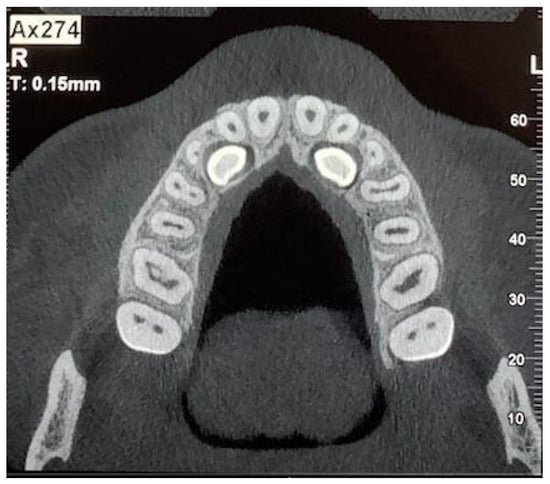

CBCT showed a palatal and osteomucosal impaction with mesio-inclination of both upper canines, close to the roots of central and lateral incisors (Figure 2).

Figure 2. Axial plane of CBCT showing palatally impacted canines. (R: right; L: left).